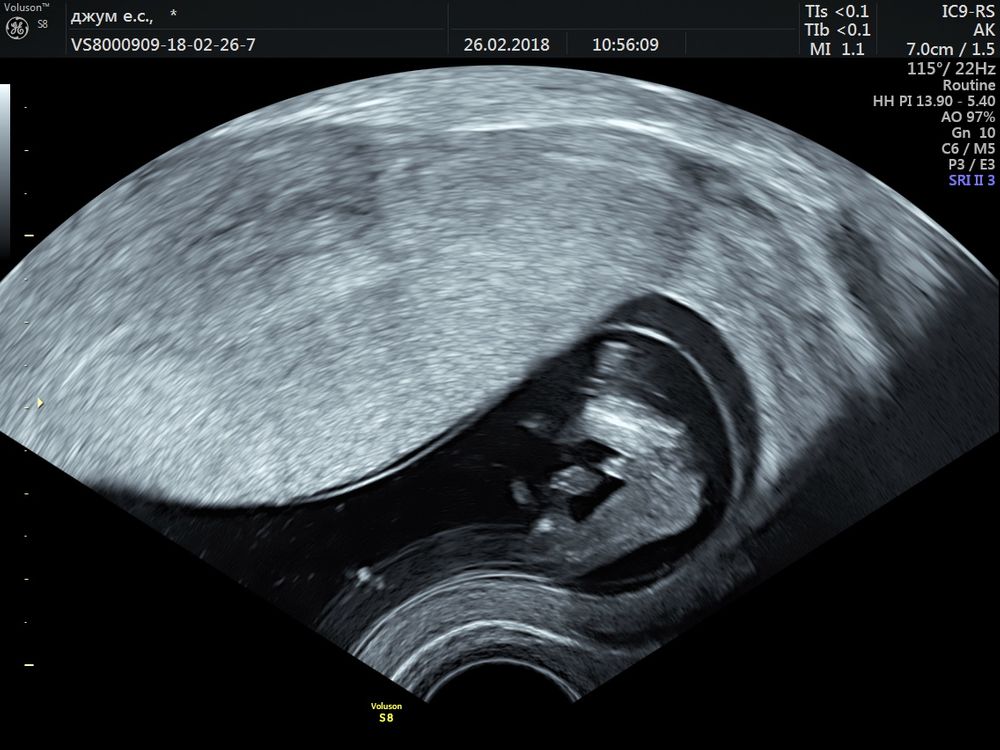

Девочки помогите 🆘 мальчик или девочка ? До 30 недель 4 разных врача утверждали что девочка ,узи на 17 неделе , а тут пошла на допплер и врач говорит что мальчик 👦 мы уже все вещи розовые купили 😅было ли у кого такое ? 30 недель снимок также прикладываю

Первое фото точно девка, а на втором скорее всего что-то примешалось, может пуповина. В общем, парнем пока не пахнет)

так писюн не видно, больше на губы похоже

На втором фото действительно похоже на мальчика. Прям мошонку хорошо видно и сам пистолетик. Напишите потом что скрининг покажет )